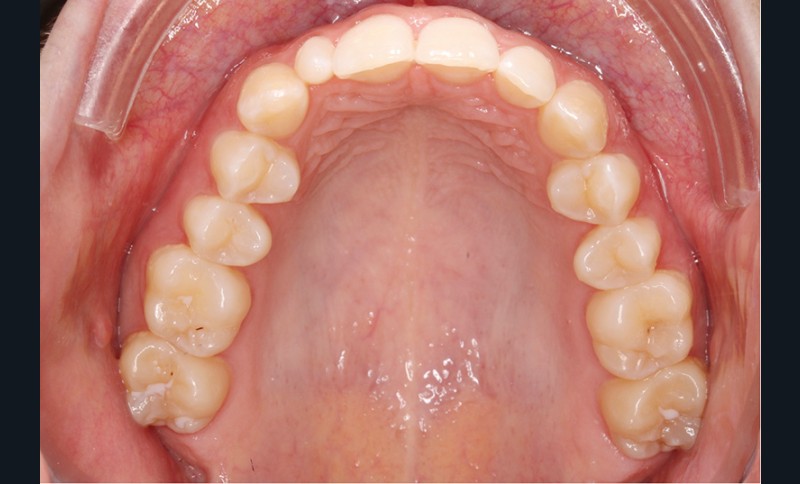

Elle présente une classe I dentaire en denture adulte. Son sourire est perturbé, notamment par la microdontie de son incisive latérale maxillaire droite (la 12). On constate un encombrement modéré au maxillaire (bimarginotopie mésio-palatine et disto-vestibulaire de 13) et plus marqué à la mandibule (monomarginotopie mésio-vestibulaire de 32 et de 43) (fig. 1-6).

Le plan de traitement a pour but d’augmenter l’espace disponible pour la restauration coronaire de 12, afin de restaurer l’esthétique du sourire, d’aligner les dents, de coordonner les milieux inter-incisifs et de modifier les angulations des incisives et des prémolaires, sans modifier les rapports molaires de classe I.